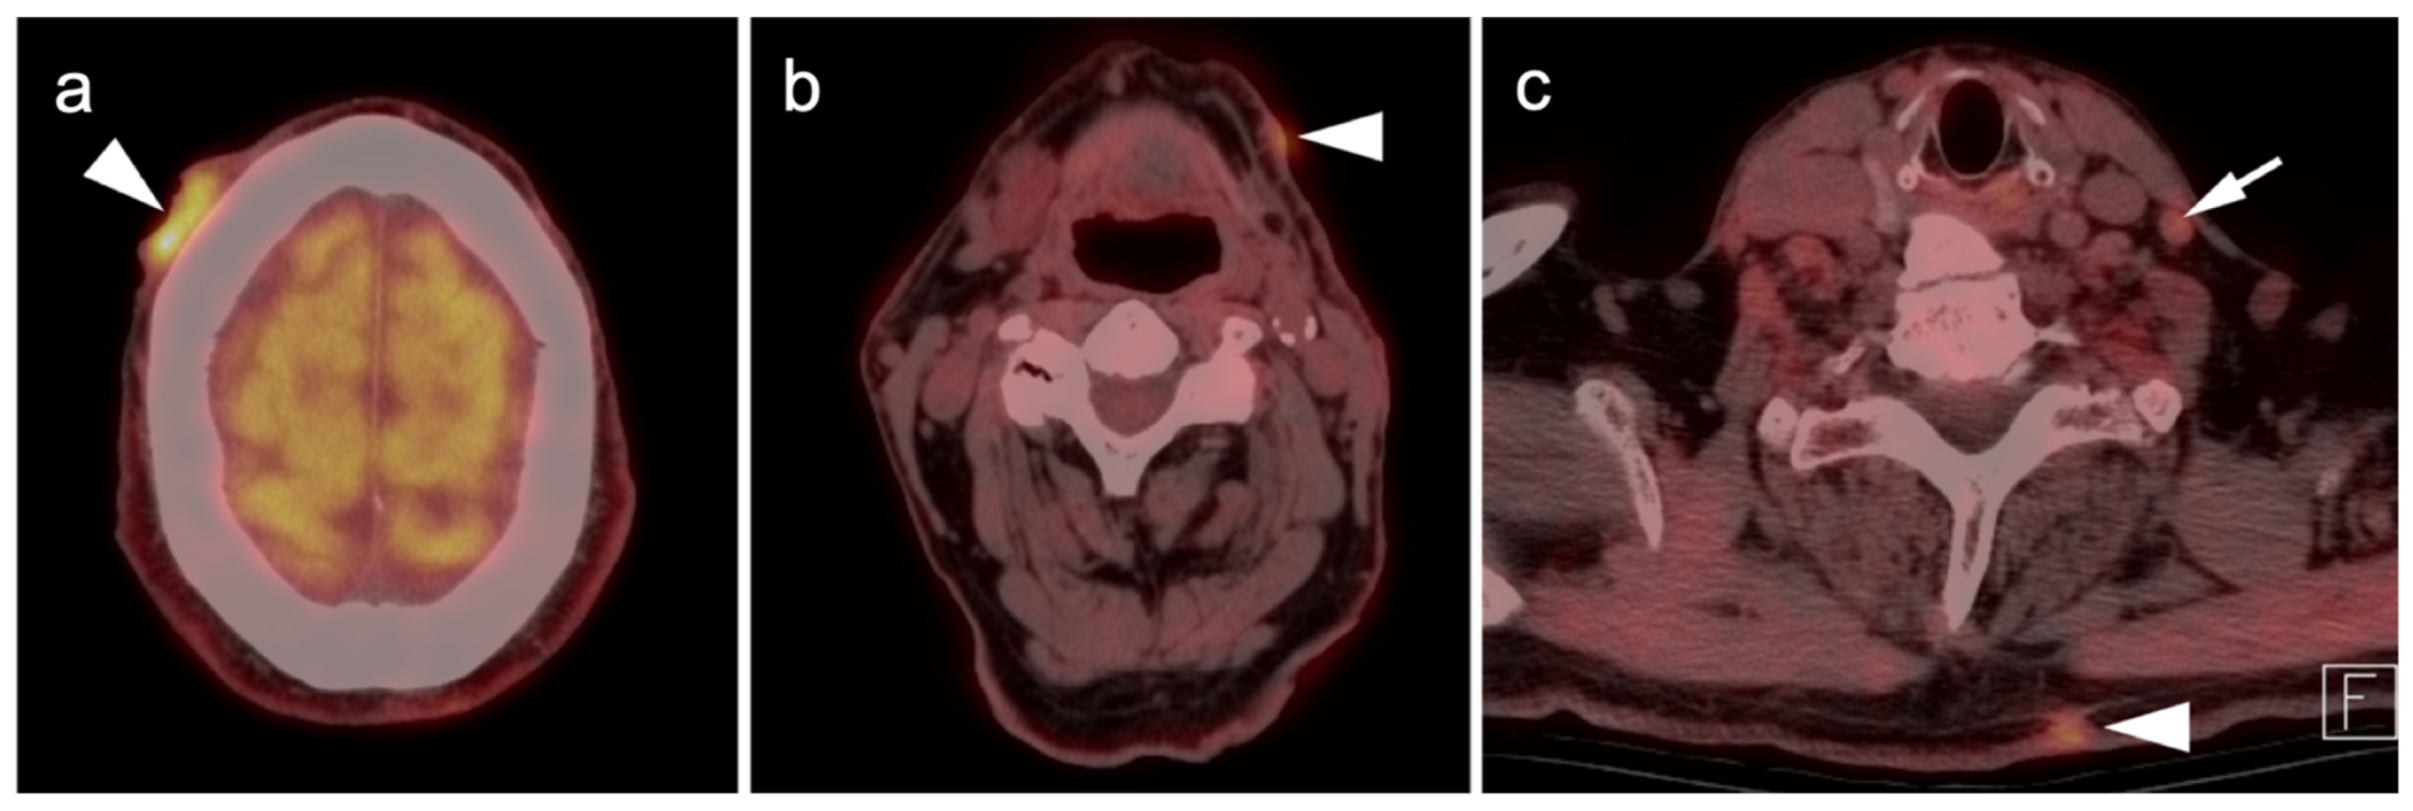

2.3.3. Mucosal Melanoma